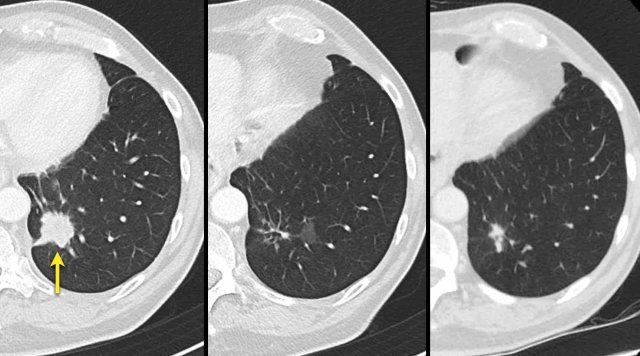

The images are of a patient with a primary lung tumour.

At baseline, the longest diameter is well above 10 mm, therefore this was assigned as a target lesion.

During follow-up the long-axis diameter dropped below 10 mm, which is the lower limit for considering a lesion as target lesion.

However, since this is a follow-up measurement, the target lesion still counts up to the sum of the diameters (SLD) and a default value of 5mm was assigned.

These CT images are of a 32-year-old male with a pulmonary metastasis of a malignant peripheral nerve sheath tumour.

Cavitation occured after treatment with pazopanib, but the size remained the same.

Although the size remains the same, a remark can be made in the report, that the actual tumorvolume has decreased.